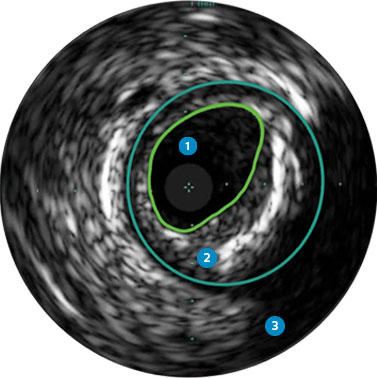

Intrasight

The IntraSight applications platform is where imaging, physiology, and software all come together to clearly identify coronary and peripheral artery disease, and allow for more optimized treatment plans.

Angiography provides information on luminal characteristics of peripheral arteries, but severely underestimates the extent of atherosclerosis in patients with PAD, even in “normal appearing” vessels.1

Guides device sizing to ensure precise wall apposition, drug delivery, and placement

Understand plaque type and severity to help guide proper device selection

Visualize plaque burden location for precise treatment

Confirm true lumen or sub-intimal guidewire location